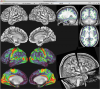

Connectome Workbench Images

3 Images available.

(click to enlarge)